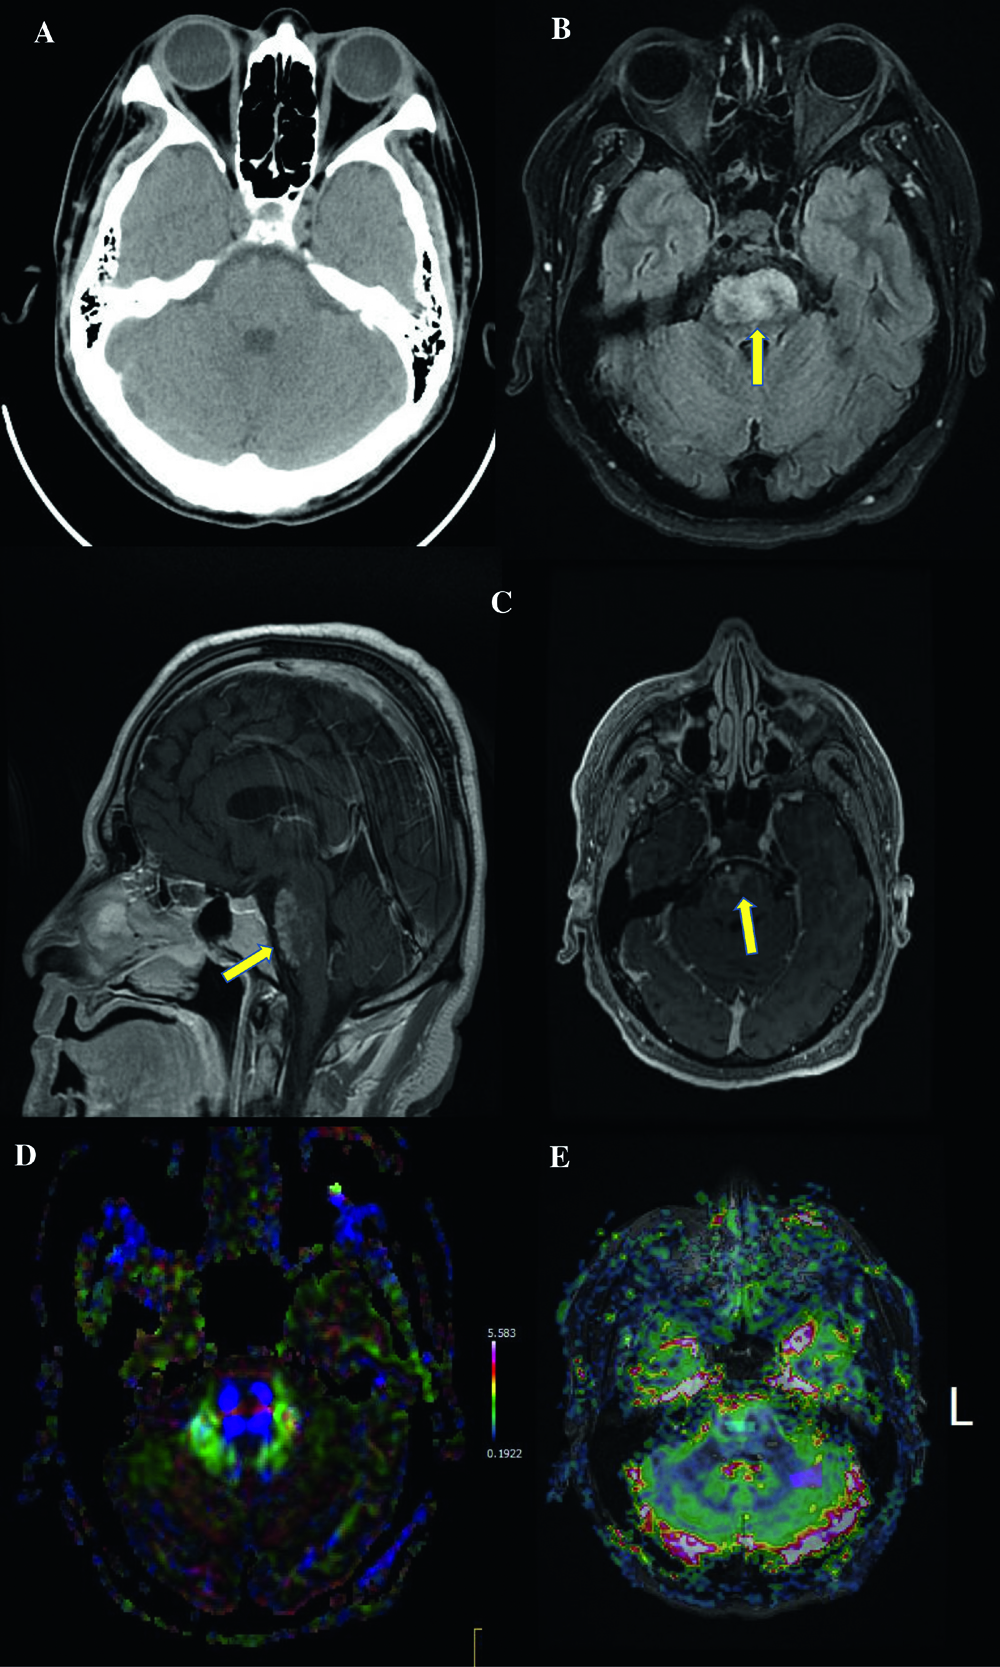

Figure 1

Figure 1. Panel A: CT brain without contrast showing no abnormality in the region of the pons. Panel B: Axial T2 FLAIR MRI image demonstrating abnormal increased T2 FLAIR signal within the ventral pons. (Arrow) Panel C: Axial T1 postcontrast image and sagittal T1 postcontrast image showing abnormal lacelike enhancement in the pons. (Arrow) Panel D: MRI Diffusion tensor imaging demonstrating normal transverse pontine fibers and corticospinal tracts within the pons with no significant mass effect. Panel E: MRI perfusion with dynamic susceptibility contrast imaging technique showing no increased cerebral blood flow within the lesion in the pons.